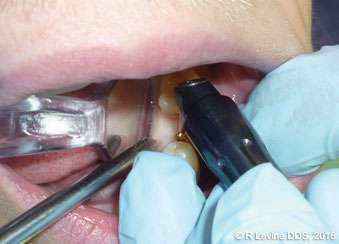

Figures 4A-4B, 5A-5B, 6A-6C, 7B-7C, and 8A demonstrate the enhanced hemostasis ensured by the LightScalpel CO2 laser. In Case 2, the patient had the vestibular extension procedure performed, and the hemorrhage was very well controlled, enabling the clinician with utmost precision. In Case 3, the bloodless excisional biopsy of fibroma was performed. Case 4 is a stage II implant uncovering procedure. This surgery requires both special accuracy and the well-controlled depth of laser energy penetration as well as enhanced hemostasis. No blood was present at any point. The implant was uncovered in approximately 30 seconds. In connection with implant uncovering, it should be mentioned that the recent study on the 10,600 nm CO2 laser removal of biofilm from titanium implant surfaces[11] reported that this laser wavelength does not affect titanium or titanium oxide (most common implant materials) and is therefore safe to use around implants. Case 5 shows a LightScalpel CO2 laser lingual frenectomy in a 7-year-old patient. Surgery is performed in a highly vascularized area where bleeding was well controlled. Finally, Case 6 is the ablation of the inflamed operculum. Figure 8A demonstrates the immediately postoperative view with excellent hemostasis.

Case 4: Stage II implant uncovering